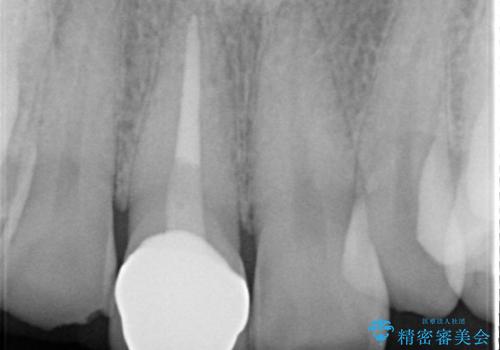

- 前歯の色が変色してきて、気になるとのことで来院されました。

オールセラミックを装着することで改善することとしました。